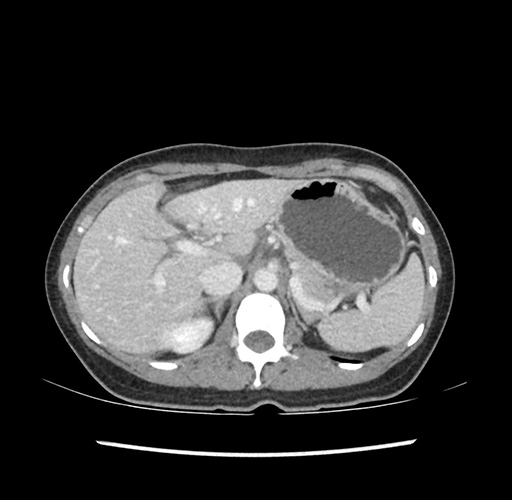

Imaging Analysis

Look through the patient's CT scan to identify any areas of concern for the necessary procedure.

Based on your CT findings, which issue(s) would give reason for "planned slowing down moment(s)" in this case?

Considering a standard left lateral sectionectomy procedure, what step(s) of the operation would you do differently in this case ?